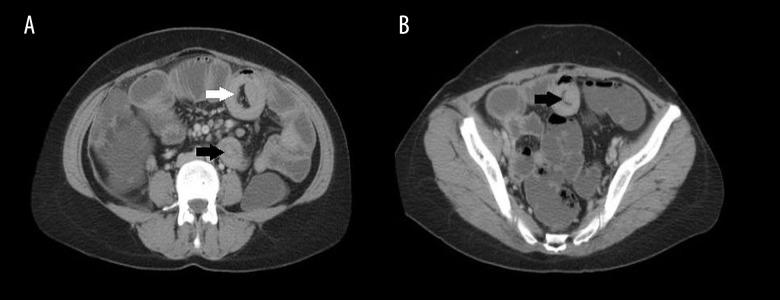

32-year-old female was admitted to Emergency Department with complaints of epigastric abdominal pain and vomiting. US identified 'target' appereance on left paramedian location at umbilical level. Contrast enhanced abdominal CT not only confirmed the enteric intussusception that was demonstrated on previos US, but also showed additional concomitant intussusceptions and inflamed appendix.

一名32岁女性因上腹部疼痛和呕吐被收入急诊科。超声检查在脐水平左旁正中位置发现“靶征”。增强腹部CT不仅证实了先前超声检查显示的肠套叠,还显示了额外并存的肠套叠和发炎的阑尾。